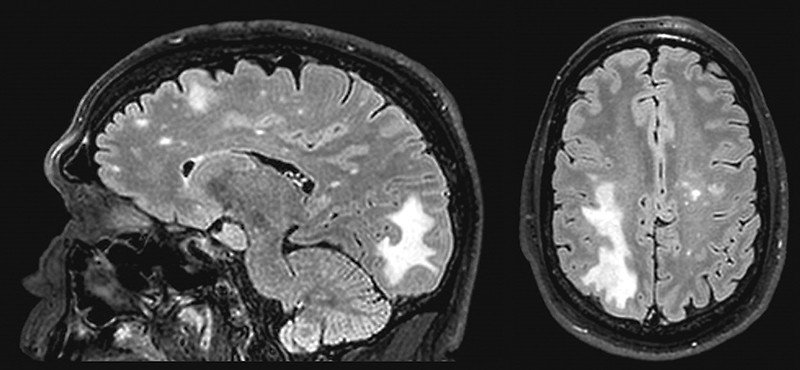

I cannot begin to describe how unpleasant a Lumbar Puncture is; my Lumbar Puncture was inconclusive, mainly because the lab “lost” the CSF sample! So the neurologist said we were going to have to do it again, to which I replied, “I’d rather boil my head in a bag.” But we still did not have a definitive diagnosis as to what was causing my limp, so he told me the only other option was brain surgery which would allow him to biopsy lesions which had shown up on a magnetic resonance imaging (MRI) scan. Brain surgery! I said, “Brain surgery? That’s like the Cadillac of surgeries; isn’t there any other…” He cut me off mid-sentence and snapped ‘no,’ saying it was either that or another Lumbar Puncture. I chose brain surgery, and was admitted to Cedars-Sinai in West Hollywood.

PML is a demyelinating disease, meaning the myelin sheath that covers the axons of nerves in the brain is destroyed. This means that when the brain sends a message by generating an electrical impulse down an axon, the message is impeded on its journey by the missing myelin and may not reach its intended destination – think of a frayed electrical cord. In that way, PML is like a disease called Multiple Sclerosis (MS), with one major difference.

In MS, the myelin is attacked and destroyed, but in PML, the myelin and the cells that produce the myelin are destroyed. Either way, “messages” like telling a leg to walk or a hand to pick up a pencil are lost, and the leg or the hand do not respond; it looks like paralysis. When the brain is sending out life-sustaining messages, like telling lungs to fill themselves with air, it really is quite serious.

PML is caused by the JC virus (which stands for “John Cunningham,” the PML patient in whom it was first identified, in 1965). JC virus (JCV) is a neurological polyomavirus, meaning – a virus affecting mammals and birds. By the age of 10, most people have been infected with JCV, but it rarely causes symptoms; the virus remains in the body, but normally is inactive and causes no problems in those with healthy, functioning immune systems. It can be “activated” (as in my case) by an HIV infection, with people on chronic immunosuppressive medications including chemotherapy also at risk of developing PML. It is fatal in 90% of cases within six months of diagnosis, meaning 10% survive and learn to live with it, left with varying degrees of neurological disabilities. I am in that 10%.